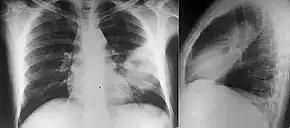

Various imaging modalities can also help with the diagnosis of melioidosis. In acute melioidosis with the spreading of the bacteria through the bloodstream, the chest X-ray shows multifocal nodular lesions. It may also show merging nodules or cavitations. For those with acute melioidosis without the spread to the bloodstream, chest X-ray most commonly shows upper lobe consolidation or cavitations.[10] In chronic melioidosis, the slow progression of upper lobe consolidation of the lungs resembles tuberculosis.[10] For abscesses located in other parts of the body apart from the lungs, especially in the liver and spleen, CT scan has higher sensitivity when compared with an ultrasound scan. In liver and splenic abscesses, an ultrasound scan shows "target-like" lesions while a CT scan shows "honeycomb sign" (abscess with loculations separated by thin septa) in liver abscesses.[10] For melioidosis involving the brain, MRI has higher sensitivity than a CT scan in diagnosing the lesion. MRI shows ring-enhancing lesions for brain melioidosis.[10]